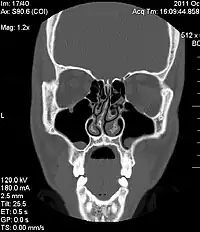

Desvio de septo nasal

Desvio do septo nasal é um distúrbio físico do nariz, envolvendo deslocamento do septo nasal.

Septo nasal é a estrutura que divide o nariz em duas narinas. Formado por ossos (na sua parte posterior) e cartilagem (na porção anterior), é revestido pelo mesmo tipo de tecido que forra internamente o nariz, conhecido por mucosa nasal.